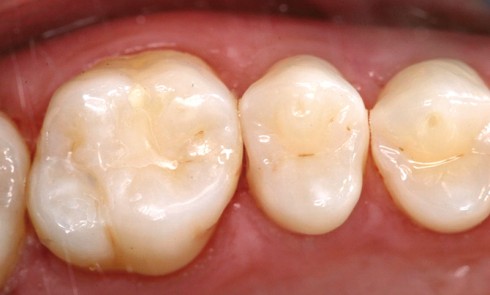

Article réservé à nos abonnés Utilisation des composites fluides pour les microcavités

S’il est admis aujourd’hui que les résines composite représentent les matériaux les plus actuels pour remplacer les tissus perdus dans...

Les scellements préventifs et thérapeutiques font partie de l’éventail des procédures cliniques appliquées à l’intervention minimale qui est le concept...